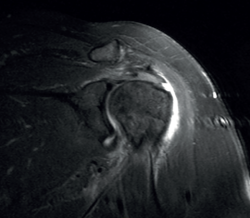

Figure 6. Severe supraspinatus tendinopathy in T2-weighted imaging.

The characteristic MRI image of tendinosis consists of a focal or intra-substance zone of intermediate signal intensity in T1-weighted imaging which does not disappear in T2 sequencing and does not reach fluid signal intensity in T2-weighted imaging (Figure 6). We can sometimes observe diffuse or focal thickening of the tendon, without evidence of rupture(33). Tendinosis may prove difficult to distinguish from early-stage partial rupture of the tendon.